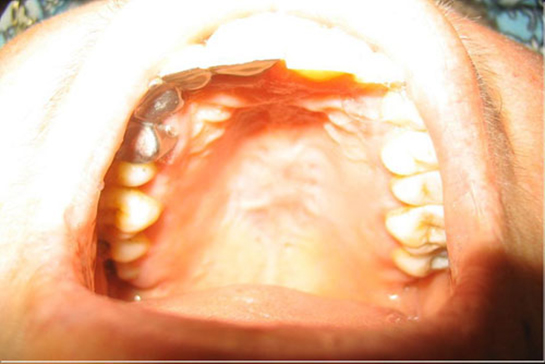

Üst Damak Şişmesi Sebepleri

Üst damak şişmesi, ağız sağlığı açısından önemli bir durumdur. Birçok nedeni olabilir; diş enfeksiyonları, alerjik reaksiyonlar, viral ve bakteriyel enfeksiyonlar, travmalar ve sistemik hastalıklar bu duruma yol açabilir. Erken teşhis ve tedavi, komplikasyonların önlenmesi için kritiktir.

Üst damak şişmesi, ağız ve diş sağlığı ile ilgili önemli bir durumdur. Bu durumun birçok nedeni olabilir ve genellikle ağız içindeki bir iltihaplanma, enfeksiyon veya diğer sağlık sorunları ile ilişkilidir. Bu makalede, üst damak şişmesinin olası sebeplerini detaylı bir şekilde inceleyeceğiz. 1. Diş Enfeksiyonları Diş enfeksiyonları, diş köklerindeki bakteriyel enfeksiyonlar nedeniyle meydana gelir. Bu tür enfeksiyonlar, dişin çevresindeki dokulara yayılabilir ve üst damakta şişmeye neden olabilir. Diş absesi, genellikle yoğun bir ağrı ile birlikte gelir ve acil tedavi gerektirir.